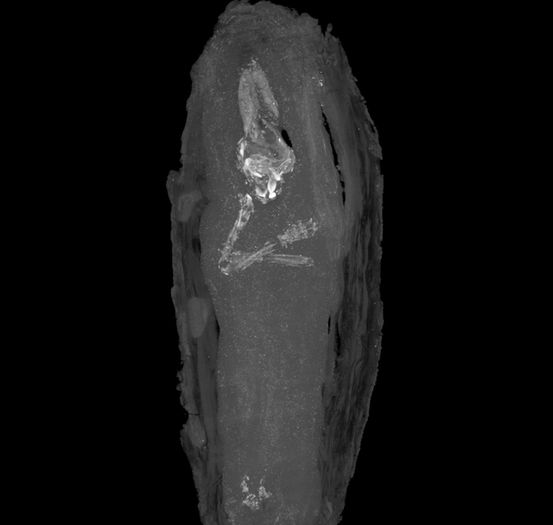

La più giovane mummia d’Egitto

Una bara in miniatura nel Fitzwilliam Museum di Cambridge (Inghilterra) conserva quella che sembra essere la più giovane mummia egizia conosciuta. La bara, fatta in legno di cedro, è stata scoperta a Giza nel 1907 e risale a oltre 2.500 anni. All’interno c’era un feto di sole 16-18 settimane dal concepimento e probabilmente morì per un aborto. La bara ha delle minuscole incisioni e si trovava nel museo da oltre un secolo, ma i curatori pensavano che contenesse degli organi interni di una qualche persona mummificata; almeno fino alla recente scansione TC che ne ha rivelato l’occupante.